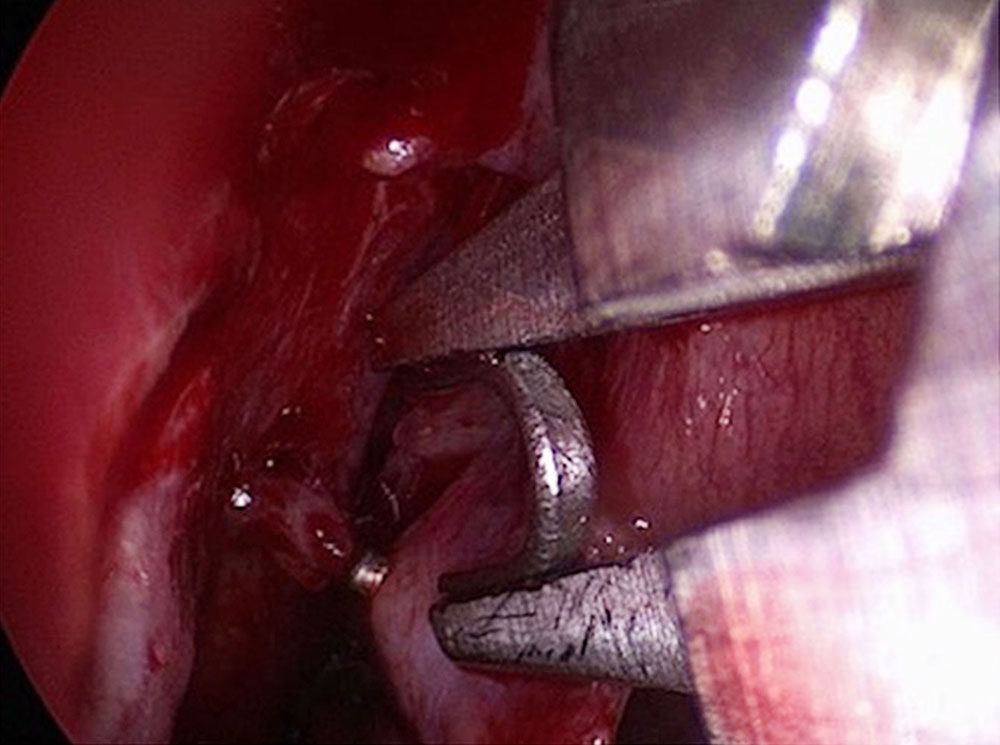

In some cases, ligation of the sphenopalatine artery is indicated at the beginning of surgery under intubation anesthesia that is intended  to control nasal bleeding. We advise electrocoagulation because recanalization restores the original anatomic situation as the disease progresses. A known feeder can then be identified again later, if necessary.